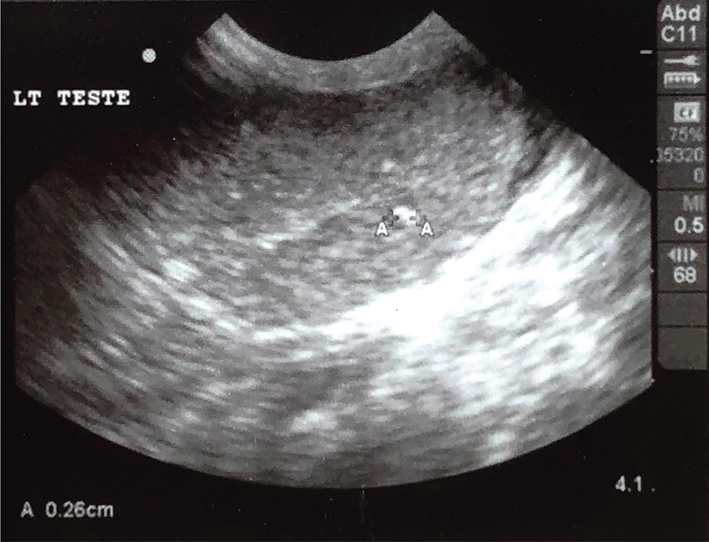

Case 2: A 3½ year, intact male Rottweiler with a history of prostate disease was presented for ultrasonographic evaluation in February of 2022. Testes were judged to be somewhat small and bilateral testicular microlithiasis was identified (Figures 5 and 6). Breeding soundness examination was performed in January of 2023. Abnormalities noted on general physical examination were mild dental disease and a grade III/VI cardiac murmur. Both testes were small, with an estimate of them being half the size expected for a dog of this breed and size. Semen was collected by manual ejaculation with no teaser female dog present but with exposure to estrous dog vaginal swabs. Libido was high; 4.5 ml of semen was collected and that was azoospermic. Semen alkaline phosphatase concentrations suggested incomplete ejaculation despite good libido and normal erection and reproductive behavior. Dog was castrated and testes were submitted for histopathology in April 2023. Both testes contained widely scattered foci (Figures 7 and 8; blue arrows) of intratubular mineralization (500 µm in maximal diameter with < 200 µm in diameter) without associated inflammation. Outside of these mineralized areas, there were rare small interstitial infiltrates of lymphocytes and plasma cells and rare individual atrophied seminiferous tubules.

Figure 5.

Figure 5. Left testicular ultrasonographic image of Case 2

Figure 6.

Figure 6. Right testicular ultrasonographic image of Case 2